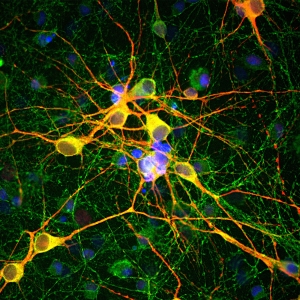

Image: Astrocytes stained with S100 beta.